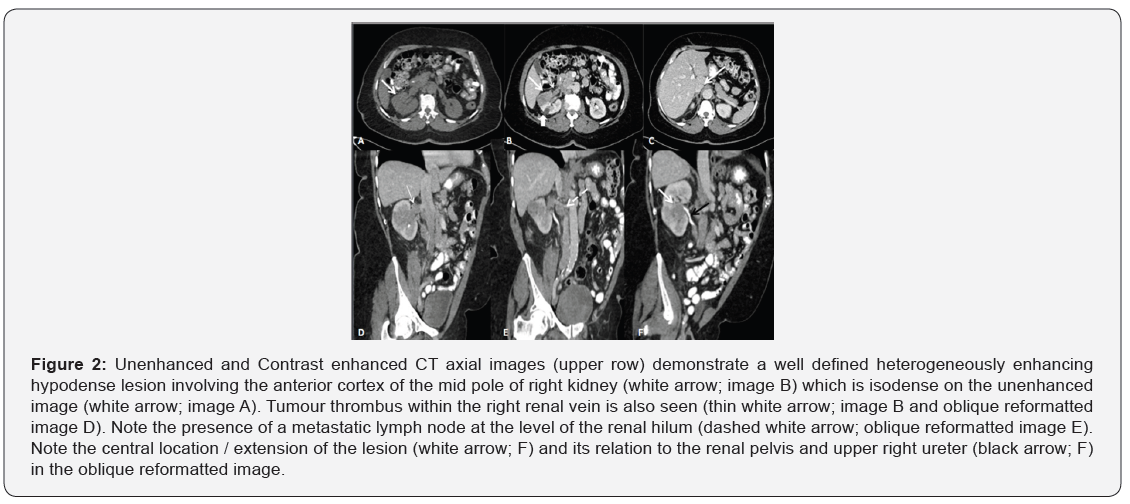

CT demonstrated a right renal hypodense lesion predominantly involving the antero-lateral aspect of the mid part of the right kidney measuring 6 x 3 cm. Peri-renal fascia appeared thickened with minimal surrounding fat stranding. Focal filling defects were noted in the right renal vein and IVC in continuity with the tumour denoting direct tumour extension/ thrombosis (Figure 2). Multiple enlarged retrocaval and aortic lymph nodes were additionally noted, suggesting metastatic involvement, cT3a N1 M0.

An MRI abdomen with intravenous contrast was performed for further characterization and assessment of the renal vein/ IVC wall invasion. On MR, an ill-defined heterogeneously enhancing infiltrative right renal mass was noted in the mid to lower pole of the right kidney. The mass was seen extending into the renal hilum and invading the renal pelvis. Tumoral thrombus was seen extending along the entire course of the right renal vein and projecting into the right side of the lumen of inferior vena cava without definite wall invasion (Figure 3). Considering direct extension of the tumour into the renal vein and IVC, a diagnosis of renal cell carcinoma was inferred. However, in view of the central location of the tumor involving the renal pelvis, upper tract transitional cell carcinoma was also listed in the differential.